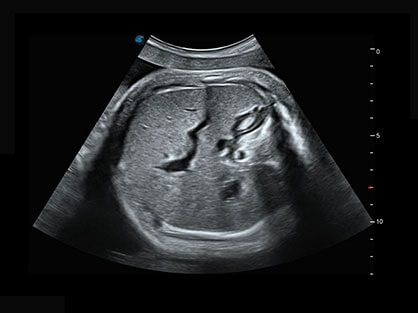

作为P系列家族成员之一,P40 Plus采用db真人体育官网高端超声系统平台——极光,并以时尚秀丽、小巧灵动的外观设计绽放出灵动之韵、科技之美。高端平台的使用保证了P40 Plus优质的基础图像;完备的高级功能可满足您全身应用的基本需求;丰富的探头配置、多样的高级4D成像及分析软件为您日益增多的妇产应用需求提供丰富的诊疗方案。

结合db真人体育官网超宽频带探头技术优势,能够更好地获得高分辨力与高穿透力的平衡,保证图像质量,为临床诊断保驾护航。

微米成像技术提升了对组织斑点噪声信号的抑制能力,并进一步强化边界信息,从而获得清晰图像。